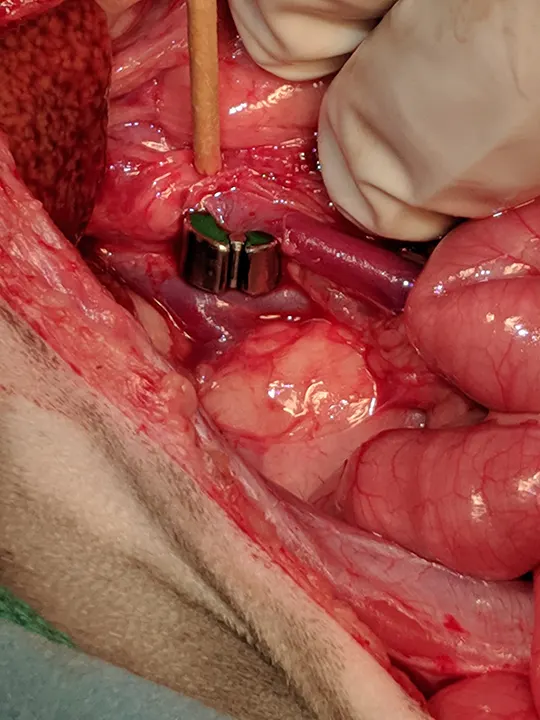

After 2 weeks, CT angiography is performed, and a splenocaval shunt (Figure 1) and multiple cystoliths are revealed. Exploratory laparotomy is performed, the splenocaval shunt is identified, and an ameroid ring constrictor is placed to achieve gradual occlusion (Figure 2). A liver biopsy is obtained, and a routine cystotomy is performed to remove the cystoliths. All samples are submitted for analysis.